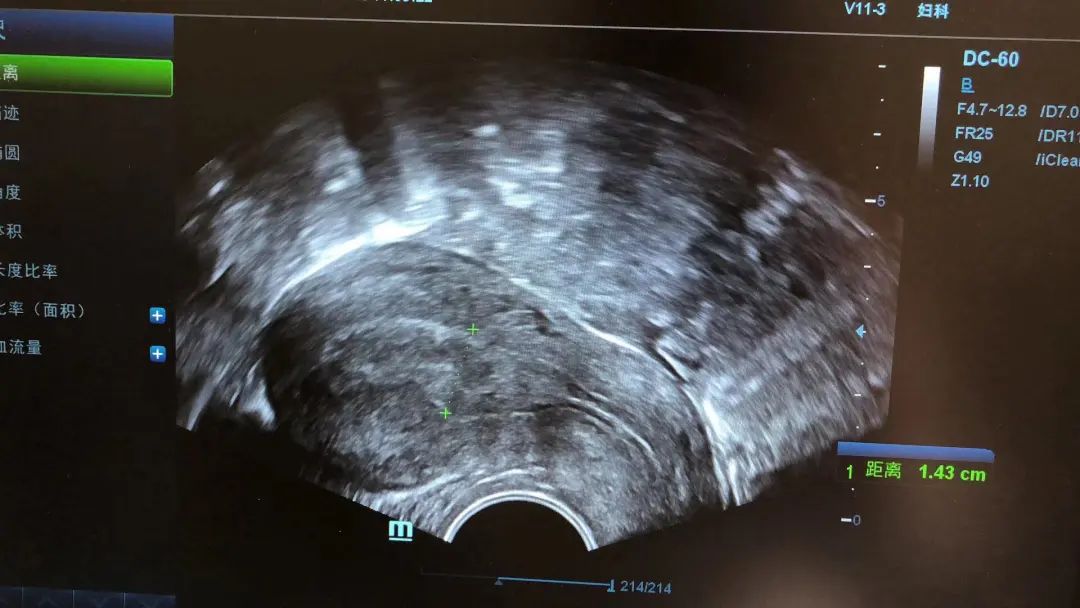

子宫内膜厚度的测量:通过阴道B超选取内膜最厚处进行测量。

在监测排卵过程中,子宫内膜会随着卵泡的生长而增厚。一般认为当子宫内膜厚度≤7 mm时,妊娠率会明显降低,同时随着子宫内膜厚度的增加,妊娠率也会相应的增加,但也不是说子宫内膜越厚妊娠率就会越好。

内膜太薄,子宫就像贫瘠的盐碱地,种不出好庄稼。内膜太厚,子宫就像一块沼泽地,也不利于种子发芽生长。临床认为8-14mm的内膜厚度是比较适合受孕的。

但单纯的子宫内膜厚度并不能作为评估能否怀孕的指标。